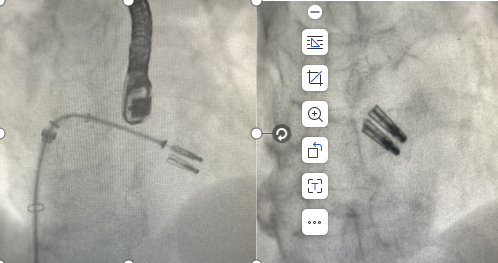

术中使用二枚二尖瓣钳子完成手术

术前,科室组织多学科会诊,由心脏大血管外科、心内科、麻醉科等多位专家共同讨论并一致认为,老人二尖瓣病变严重,同时合并有冠心病、心律失常、心功能不全等多种高危因素,已不适用外科手术,在微创下不开胸实施二尖瓣钳夹术是最佳选择。经手术团队充分缜密的术前准备,在超声引导下器械经股静脉穿刺房间隔,将MitraClip系统送入患者左心房,到达二尖瓣反流处,在经食道超声及DSA引导下,术者通过评估二尖瓣反流位置、抓捕位置、反流程度,精准夹合,成功植入2个二尖瓣夹。二尖瓣从术前的大量反流减轻到微量反流,肺静脉的逆流完全消失,血压从偏低恢复到正常状态,第二天即下床,术后第5天顺利出院。